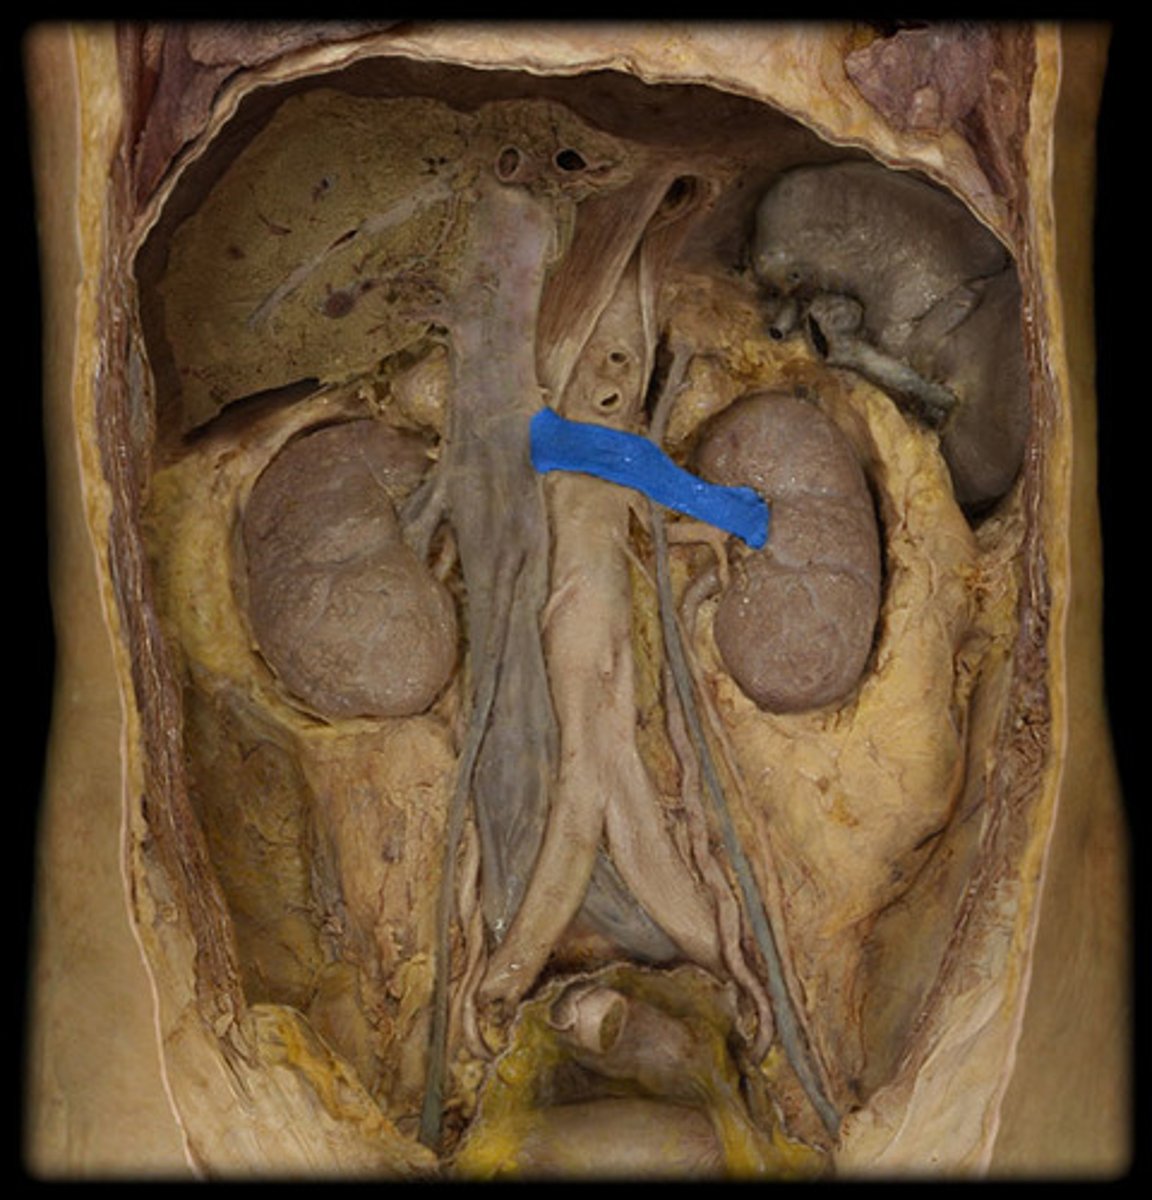

left renal vein

Which structure is highlighted and indicated by the leader line?